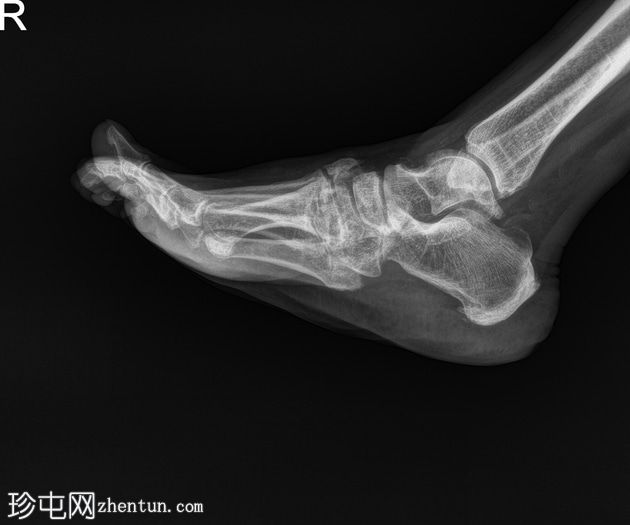

侧位片

双足均符合典型的夏科氏关节病特征,该患者为已知糖尿病患者。

该病表现为骨质疏松、骨硬化(密度改变)、跗骨碎裂和破坏、关节内游离体(碎屑)、软组织肿胀和关节积液(扩张)、中足结构紊乱以及跗跖关节错位(脱位)。

X线平片未见气性坏疽或化脓性关节炎的证据。

右足足底跟骨可见退行性骨刺和附着点病变。